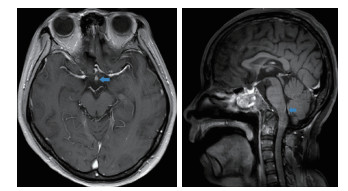

对患者再次进行神经系统查体:患者神志清楚,查体配合,智能可。双眼闭合力弱,双侧水平注视时可见持续粗大水平眼震,咬合力弱,转头耸肩力量可,四肢肌力5-级,膈肌与肋间肌肌力正常,痛觉大致正常,双上肢腱反射+++,双髌阵挛阳性,跟腱反射+++,双侧病理征阳性,颈以下皮肤划痕征阳性。因双眼闭合力弱,水平眼震,发病时呕吐,患者病变定位于脑桥背侧及小脑联系纤维;吞咽困难、球麻痹、呼吸障碍,定位于延髓背侧;前胸后背疼痛、皮肤划痕征阳性,定位于高颈段。2018年5月24日行脑脊液穿刺检查,脑脊液呈无色透明状,压力120 cmH2O。脑脊液常规:潘氏反应阴性,细胞总数3×106/L,白细胞2×106/L,红细胞1×106/L;脑脊液生化:蛋白0.4 g/L,氯离子124 mmol/L,糖5.58 mmol/L;脑脊液外送检验结果以及住院期间其他外送检验结果见表 4。其中脑脊液抗水通道蛋白抗体(AQP4-IgG)3+。2018年5月31日患者头颅磁共振检查提示:视神经分叉部、颈髓-延髓移行区异常对比增强(图 3)。结合患者临床表现,脑脊液AQP4-IgG阳性,以及头颅磁共振结果,患者最终诊断视神经脊髓炎谱系疾病。该患者后续经过激素维持治疗及康复锻炼于2018年6月5日拔除气管插管,患者吞咽功能逐渐恢复于2018年7月10日拔除胃管,2018年9月20日患者病情进一步好转出院。出院后3个月随访,患者一般情况好,生活自理,未遗留视力及其他器官功能障碍。

图 3 患者头颅增强磁共振结果(蓝色箭头标注处高密度影为患者病变所在,分别位于视神经分叉部以及颈髓-延髓移行区)